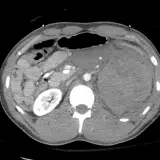

Over 2,100 interactive radiology cases, curated by radiologists for your level of training. Scroll, window, and view cases full screen — just like on PACS. Click linked findings in each writeup to jump straight to them on the image. Cases include sample reports, a focused discussion section, original illustrations, and videos.

PACSで期待されるツールを完備した完全インタラクティブな症例 — スクロール、ウィンドウ調整、ズーム、パン、計測、ROI、フルスクリーンモード。

重要な所見を症例画像上に直接ハイライトする豊富なアノテーション。症例解説内のリンクされた所見をクリックすると、スキャン上の正確な位置へジャンプできます。

職場のPACSステーションと同じようにスクロール、パン、ウィンドウ調整、ズームが可能

アノテーション付きの画像所見とイラストで効率的に学習